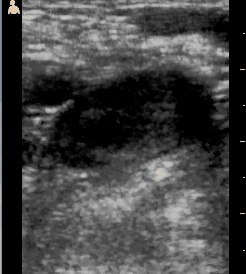

A patient who had fevers and had been in the hospital the previous week with them came to the clinic because he hadn't gotten better. He had an even higher fever and abdominal pain. His thin abdomen clearly had a lump in it. Ultrasound showed that it was a fluid filled mass about the size of a large grapefruit in his liver.

The lump was a liver abscess and in South Sudan the most common cause of this is an intestinal parasite called Entamoeba histolytica, or ameba for short. He was treated with a common antibiotic, metronidazole, and was significantly better the next day. His pain and his lump persisted, though. We worried that he might not be improving, but on the fourth day he felt much better and the lump, which had stayed big all this time, had shrunk to half its size. By the time I left he was looking like a normal guy. Small miracles.